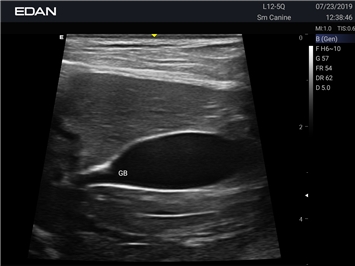

Ветеринарный ультразвук одним нажатием. Система Acclarix AX2 VET разработана с целью обеспечить бескомпромиссную производительность по доступной цене. Наличие уникальных двойных аккумуляторов в легком корпусе массой 4,5 кг из магниевого сплава позволяет системе Acclarix AX2 VET удовлетворять все потребности ветеринарных исследований, сохранив низкую стоимость.

EDAN Acclarix AX2 VET представляет собой специализированную ветеринарную ультразвуковую систему, сочетающую высокую производительность с доступной ценой. Благодаря продуманной конструкции и передовым технологиям, система обеспечивает качественную диагностику животных различных видов.

• Высокое разрешение для детальной диагностики

• Улучшенная визуализация глубоко расположенных органов

B-режим, Двухмерное сканирование:

Да